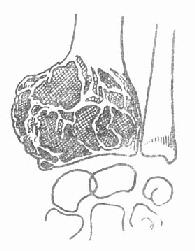

X线片表现:骨骺处有局限的囊性改变,一般呈溶骨性破坏,也可有“肥皂泡”样改变(图3-232),其扩展一般为软骨所限。不破入关节,少有骨膜反应,肿瘤范围清楚,初发时病变在骨骺内旁侧,发展后可占骨端的全部,骨皮质膨胀变薄,有的可以穿破,进入软组织。X线片可显示其一般特点,但仍不足以确诊。

图3-232 桡骨下端巨细胞瘤